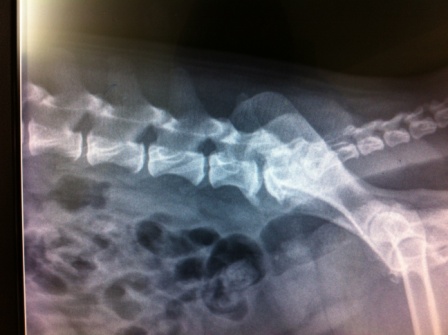

Con una cervicalgia que apareció de repente, ese macho Caniche de 9 años mantiene su cuello hacia la derecha. El primer día, una radiografía sin prepar...